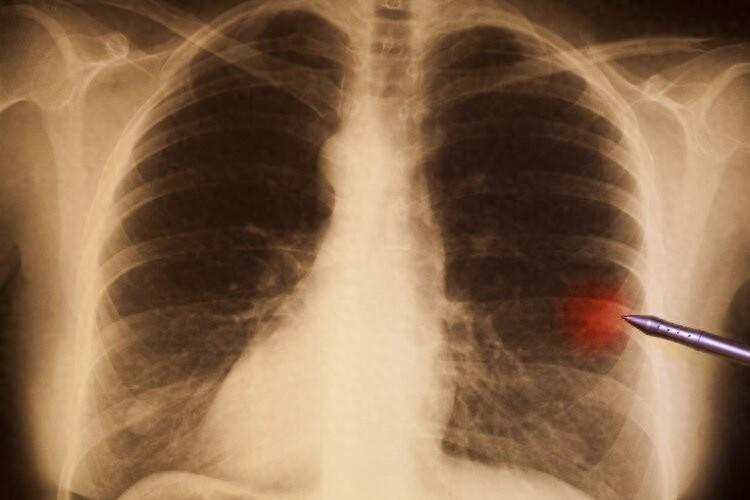

3、結節

結節其實不是疾病的診斷,而是指影像學的一個結果,可能是局部發炎、陳舊炎症、組織增生,也可能是腫瘤。體檢中最爲多見的結節爲甲狀腺結節、乳腺結節以及肺部結節,大部分結節都是良性的,保持定期隨訪即可。但如果檢查字樣中有毛刺、分界不清、豐富血供等字樣,或是在短時間內大幅度變大,則要警惕可能是惡性的。